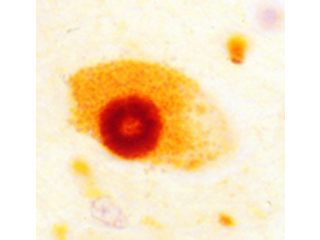

Most notably, rare pathogenic mutations have been identified in the amyloid precursor protein, microtubule associate protein tau, and alpha-synuclein genes, encoding the primary constituents of the defining disease pathologies (amyloid plaques and Tau neurofibrillary tangles in AD, and Lewy bodies in PD, respectively). We have participated in several studies that further illustrate the power of endophenotypes for functional genetic dissection of AD (Shulman et al. 2010; De Jager, Shulman et al. 2012). We have also contributed to genome-wide association studies (GWAS) seeking novel susceptibility loci for AD neuropathologic traits, including amyloid neuritic plaques and Tau neurofibrillary tangles. Our recent work finds that the association of several genes with AD susceptibility, including CR1, CD2AP, and ABCA7, is likely mediated by an impact on underlying amyloid pathology; and further, our genome scan implicates common variation in the amyloid precursor protein (APP) gene (Shulman et al. in press).

Although two percent of the population over age 65 are clinically diagnosed with PD, the defining pathology of disease (alpha-synuclein Lewy bodies) is discovered in 20 percent of brains from population-based autopsy studies. We have participated in studies to better understand the clinical impact of this pathology, and its potential as an endophenotype for genetic analyses. In a study of 744 autopsies from older adults without a clinical diagnosis of PD, nearly a third showed evidence of post-mortem Lewy bodies and/or substantia nigra neurodegeneration, the defining pathologies of PD, and these changes were associated with parkinsonian motor signs proximate to death (Buchman et al. 2011). Therefore, PD-related pathology appears to be responsible for a much greater burden of age-related motor disability than currently realized. Discovery of the underlying genetic factors may allow us to identify susceptible individuals and ultimately intervene with effective therapies.